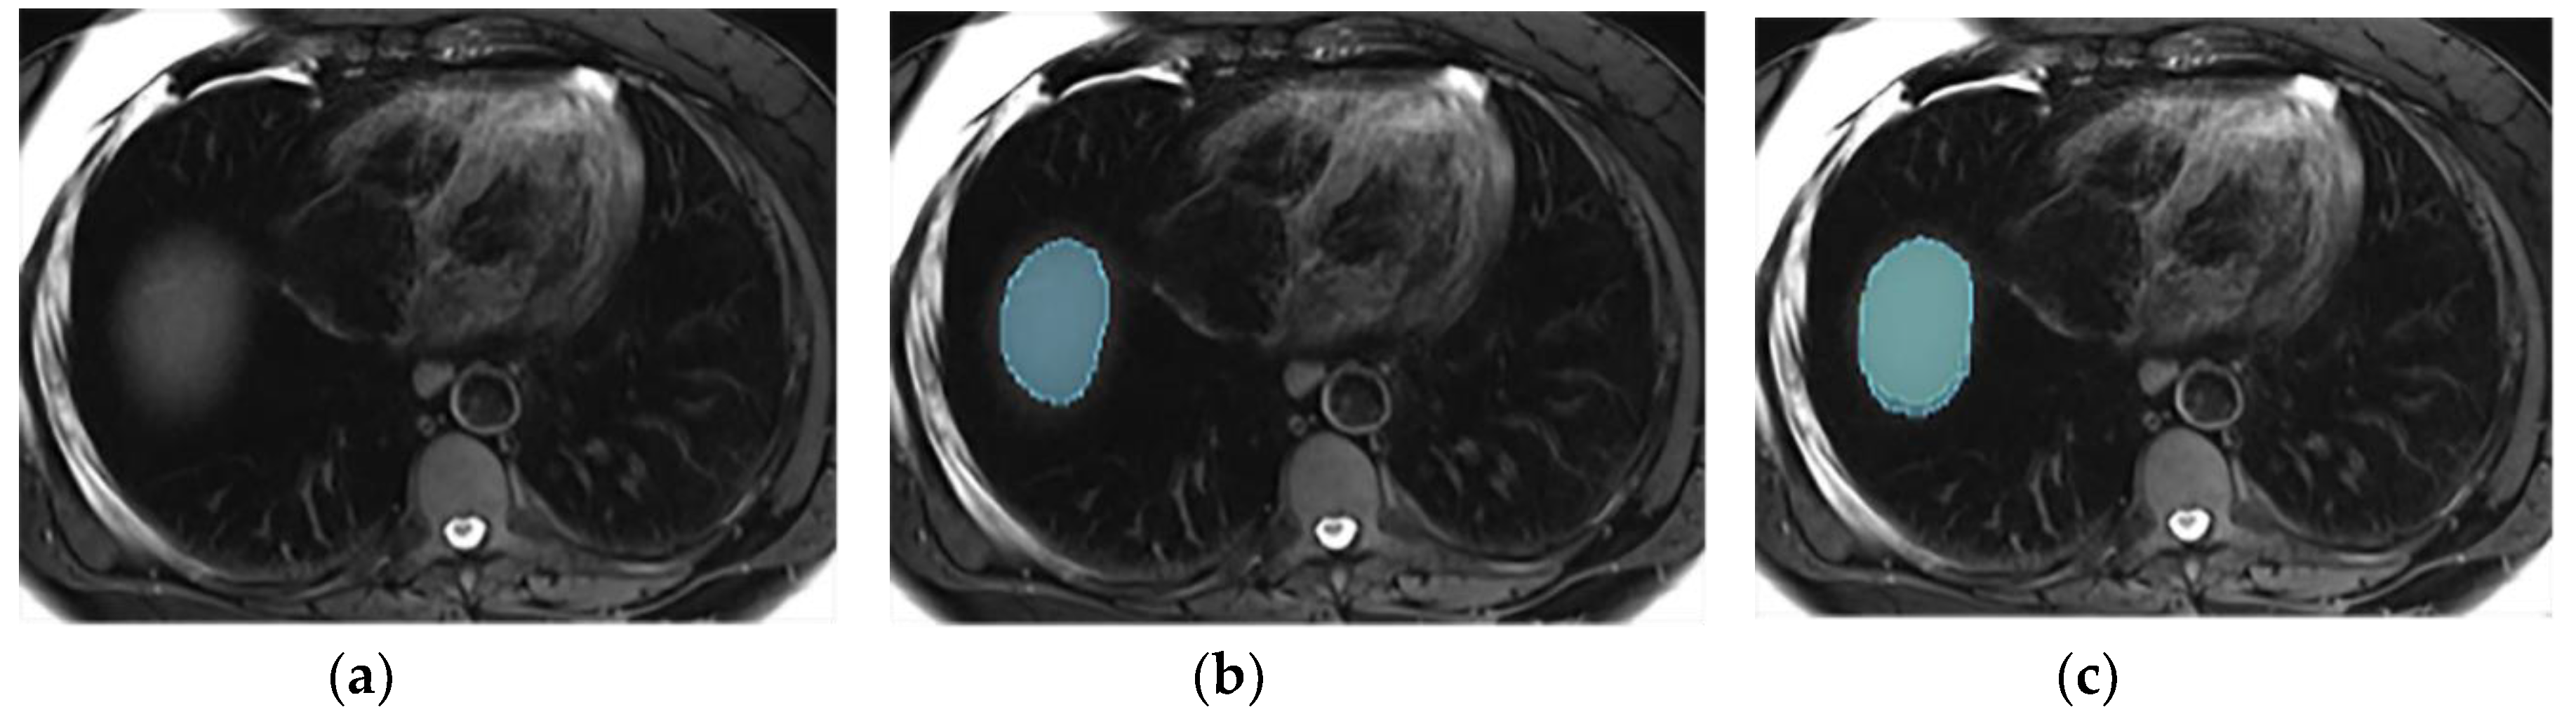

This section illustrates the segmentation process, presenting MRI liver segmentation slices created by the annotators. Examples are provided in Figure 2, Figure 3, Figure 4 and Figure 5.

Figure 2. Examples of liver segmentations on T2wi (a-c) illustrated in blue (first annotator) and green (second annotator) before (b) and after (c) protocol implementation. This figure illustrates the importance of excluding the hepatic hilum and the variation in margin taken by the annotators at the border of the liver. Before protocol implementation (b), each annotator segmented the liver with their own style, one including the hilum (green segmentation) while the other did not (blue segmentation). Additionally, one annotator (blue segmentation) took a larger margin than the other at the border of the liver. After protocol implementation (c), these differences were lessened, improving the precision of the liver delineation and the inter-reader agreement.